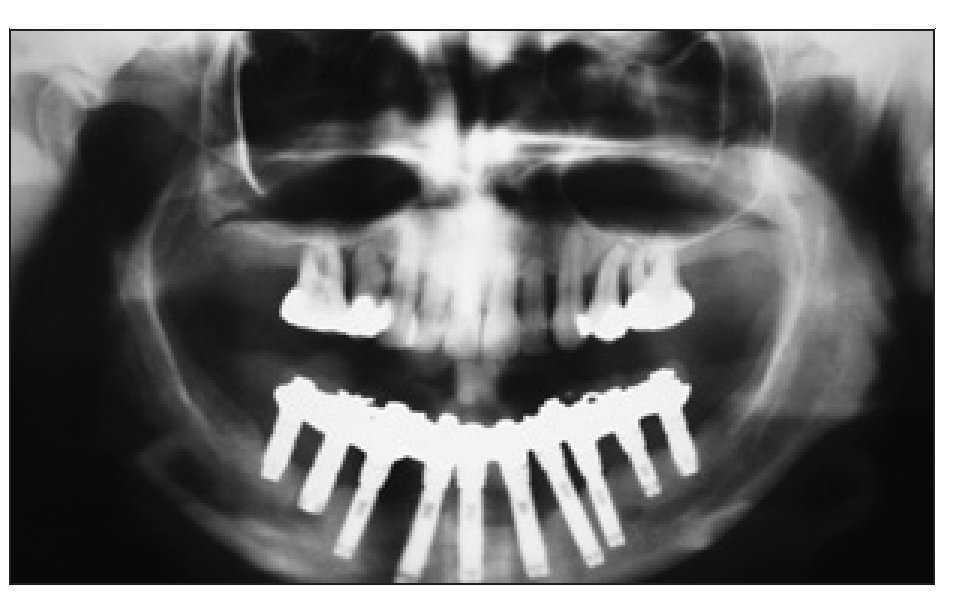

Figura 2 Ortopantomograma realizado en 1994 que muestra el tratamiento de la paciente con una PDF implantosoportada en el maxilar inferior y la retención de los dientes en el maxilar superior.